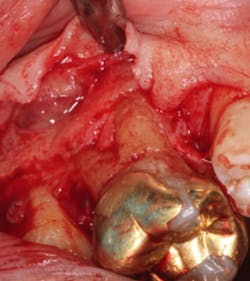

A split- to full-thickness intrasulcular incision was made on the facial of teeth Nos. 2 through 4. Upon completion of flap elevation, an intraosseous cyst associated with the distobuccal root of No. 3 was noted perforating the buccal plate and adherent to the overlying flap (figure 2). A sharp dissection separated the cyst from the flap (figure 3), and the cyst—measuring roughly 1.0 x 0.75 x 0.5 cm—was enucleated intact, leaving an intraosseous defect (figures 4a and 4b).